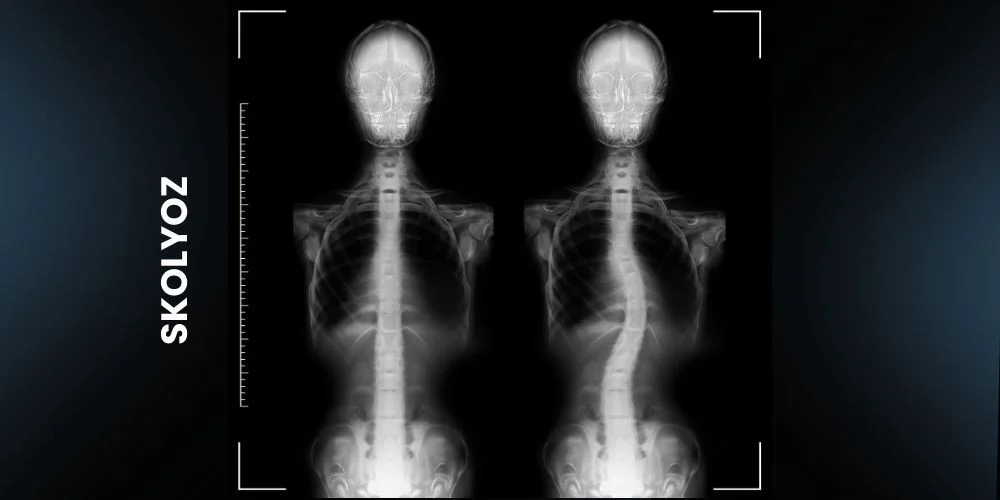

Skolyoz, omurganın yana doğru eğriliği olarak tanımlanır. Bu eğrilik genellikle ergenlik döneminde, büyüme atağı sırasında fark edilir. Skolyozun erken teşhisi, ilerlemesini durdurmak ve tedavi seçeneklerini değerlendirmek açısından büyük önem taşır.

Skolyoz teşhisi genellikle fizik muayene ve röntgen ile konulur. Fizik muayenede, doktorunuz omurganızdaki eğriliği ve duruşunuzdaki asimetriyi değerlendirir. Röntgen, omurganın detaylı bir görüntüsünü sağlayarak eğriliğin derecesini belirlemeye yardımcı olur.